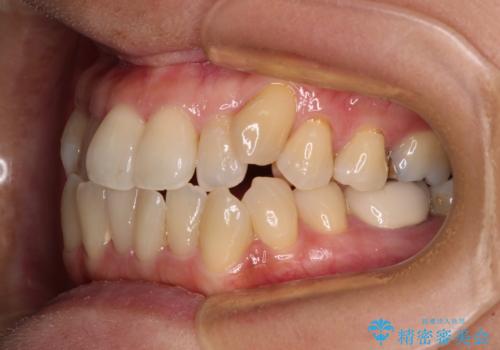

受け口と八重歯を改善 インビザライン矯正治療

- 前歯のデコボコや八重歯を治したいとのことで来院された患者様です。

受け口傾向の骨格であり、前歯はクロスバイトまたは切端咬合となっており、下顎を中心に歯列全体の後方移動を行い、IPR(歯と歯の間を削る)によってデコボコが解消するように設計し、インビザラインにより治療を行うこととしました。

受け口傾向のインビザライン矯正は比較的治療を行いやすいため、きれいに仕上げることができました。舌の突出癖が顕著であったため、改善のためのトレーニングをしっかりと行っていただきました。